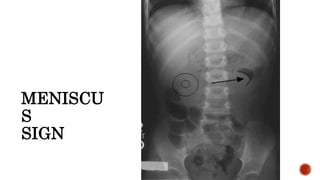

 Meniscus sign:

 Crescent of gas within colonic lumen that outlines the apex of intussusceptum.

 Little air in small intestine.

MENISCU

S

SIGN

 Convex intraluminal mass.

 May benormal.  Meniscus sign:  Crescent of gas within colonic lumen that outlines the apex of intussusceptum.  Little air in small intestine.